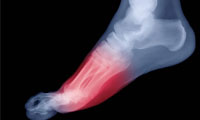

پا درد

16 درمان براى پا درد